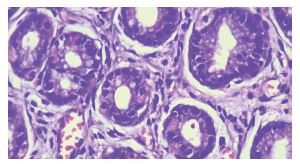

The most common histopathological diagnosis was chronic gastritis, accounting for 91.9% of cases (Figure 3). Approximately 5.1% of biopsies were diagnosed as gastric malignancy, the most frequent histological subtype being signet-ring carcinoma. Dysplasia without any clinical suspicion of malignancy was observed in 0.8% of cases, while atrophic gastritis was identified in 0.6%. Chronic gastritis was associated with additional pathological findings such as activity (3%), intestinal metaplasia (1.8%), and ulceration (0.5%).